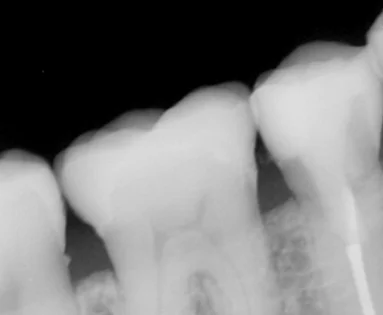

適合を確認するために撮影したレントゲンがこちらになります。

前後の歯に歯石がついているのが気になるところではありますが・・・

適合自体は問題なく、綺麗に隙間なく入っているのがわかるかと思います。 仮歯の時点で噛んだ時の痛みは消えていたので、安心してセラミックに出来ましたね。